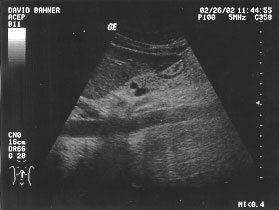

Aorta longitudinal (unlabeled)